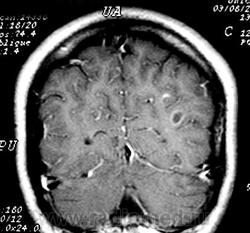

ГМ. Рассеянный склероз 3. +

Рассеянный склероз